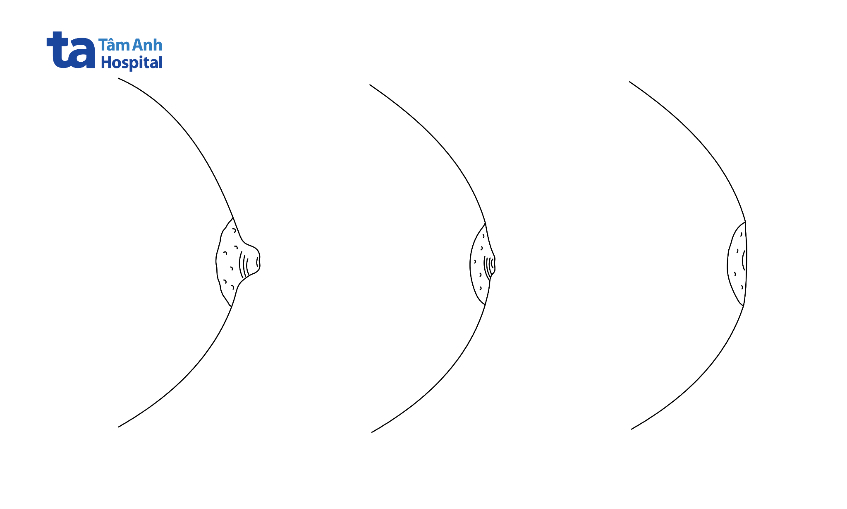

Đây là tình trạng núm vú bị tụt ra sau. Có 2 thuật ngữ là núm vú lộn ngược (inverted nipple) và núm vú co rút (retracted nipple) đều dùng để chỉ tình trạng núm vú bị thụt, thường được dùng đồng nhất và lẫn lộn với nhau nhưng điều này không chính xác.

Núm vú co rút là tình trạng một vùng ở trung tâm núm vú bị kéo vào trong và hình thành 1 rãnh nhỏ.

Núm vú lộn ngược là tình trạng toàn bộ núm vú bị kéo ngược ra sau, có thể ra sau khỏi mặt phẳng của quầng vú. Cả 2 tình trạng này đều có thể mang tính bẩm sinh hoặc mới mắc phải và có thể xuất hiện 1 bên hoặc cả 2 bên vú.

Núm vú bị thụt 2 bên có thể là biến thể bình thường của núm vú, diễn ra từ từ hoặc kéo dài nhiều năm và thường lành tính. Nếu người bệnh mới bị núm vú bị thụt 1 bên cần đi khám sớm vì khả năng cao bị viêm nhiễm hay thậm chí là bệnh ác tính tiềm ẩn. Những bệnh được chẩn đoán khi núm vú bị thụt 1 bên là lao vú, giãn ống tuyến vú, viêm vú quanh ống dẫn sữa hoặc ung thư vú.

Trung tâm núm vú bị co rút đồng dạng tạo thành 1 rãnh nhỏ thường lành tính nhưng nếu toàn bộ núm vú bị thụt làm di lệch quầng vú thường là triệu chứng của bệnh ác tính.